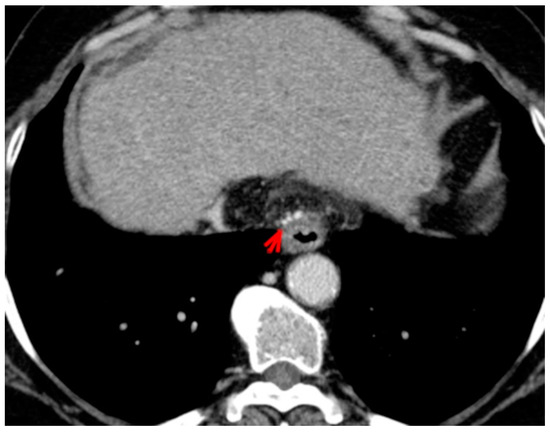

For this study, the images were retrospectively analyzed in consensus by two readers with experience in the field of abdominal imaging. The two readers assessed the following CT features: (1) The presence or absence of paraoesophageal varices and the size(mm) of the largest varix (Figure 1); (2) the presence or absence of paragastric varices and the size (mm) of the largest varix (Figure 2); (3) the largest diameter of the left gastric vein (Figure 3); (4) the presence or absence of splenorenal shunts and the size(mm) of the shunt (Figure 4); (5) the presence or absence of a repermeabilized round ligament and the size(mm) of it (Figure 5).

Figure 3. Axial contrast-enhanced CT shows enlarged left gastric vein (red arrow).